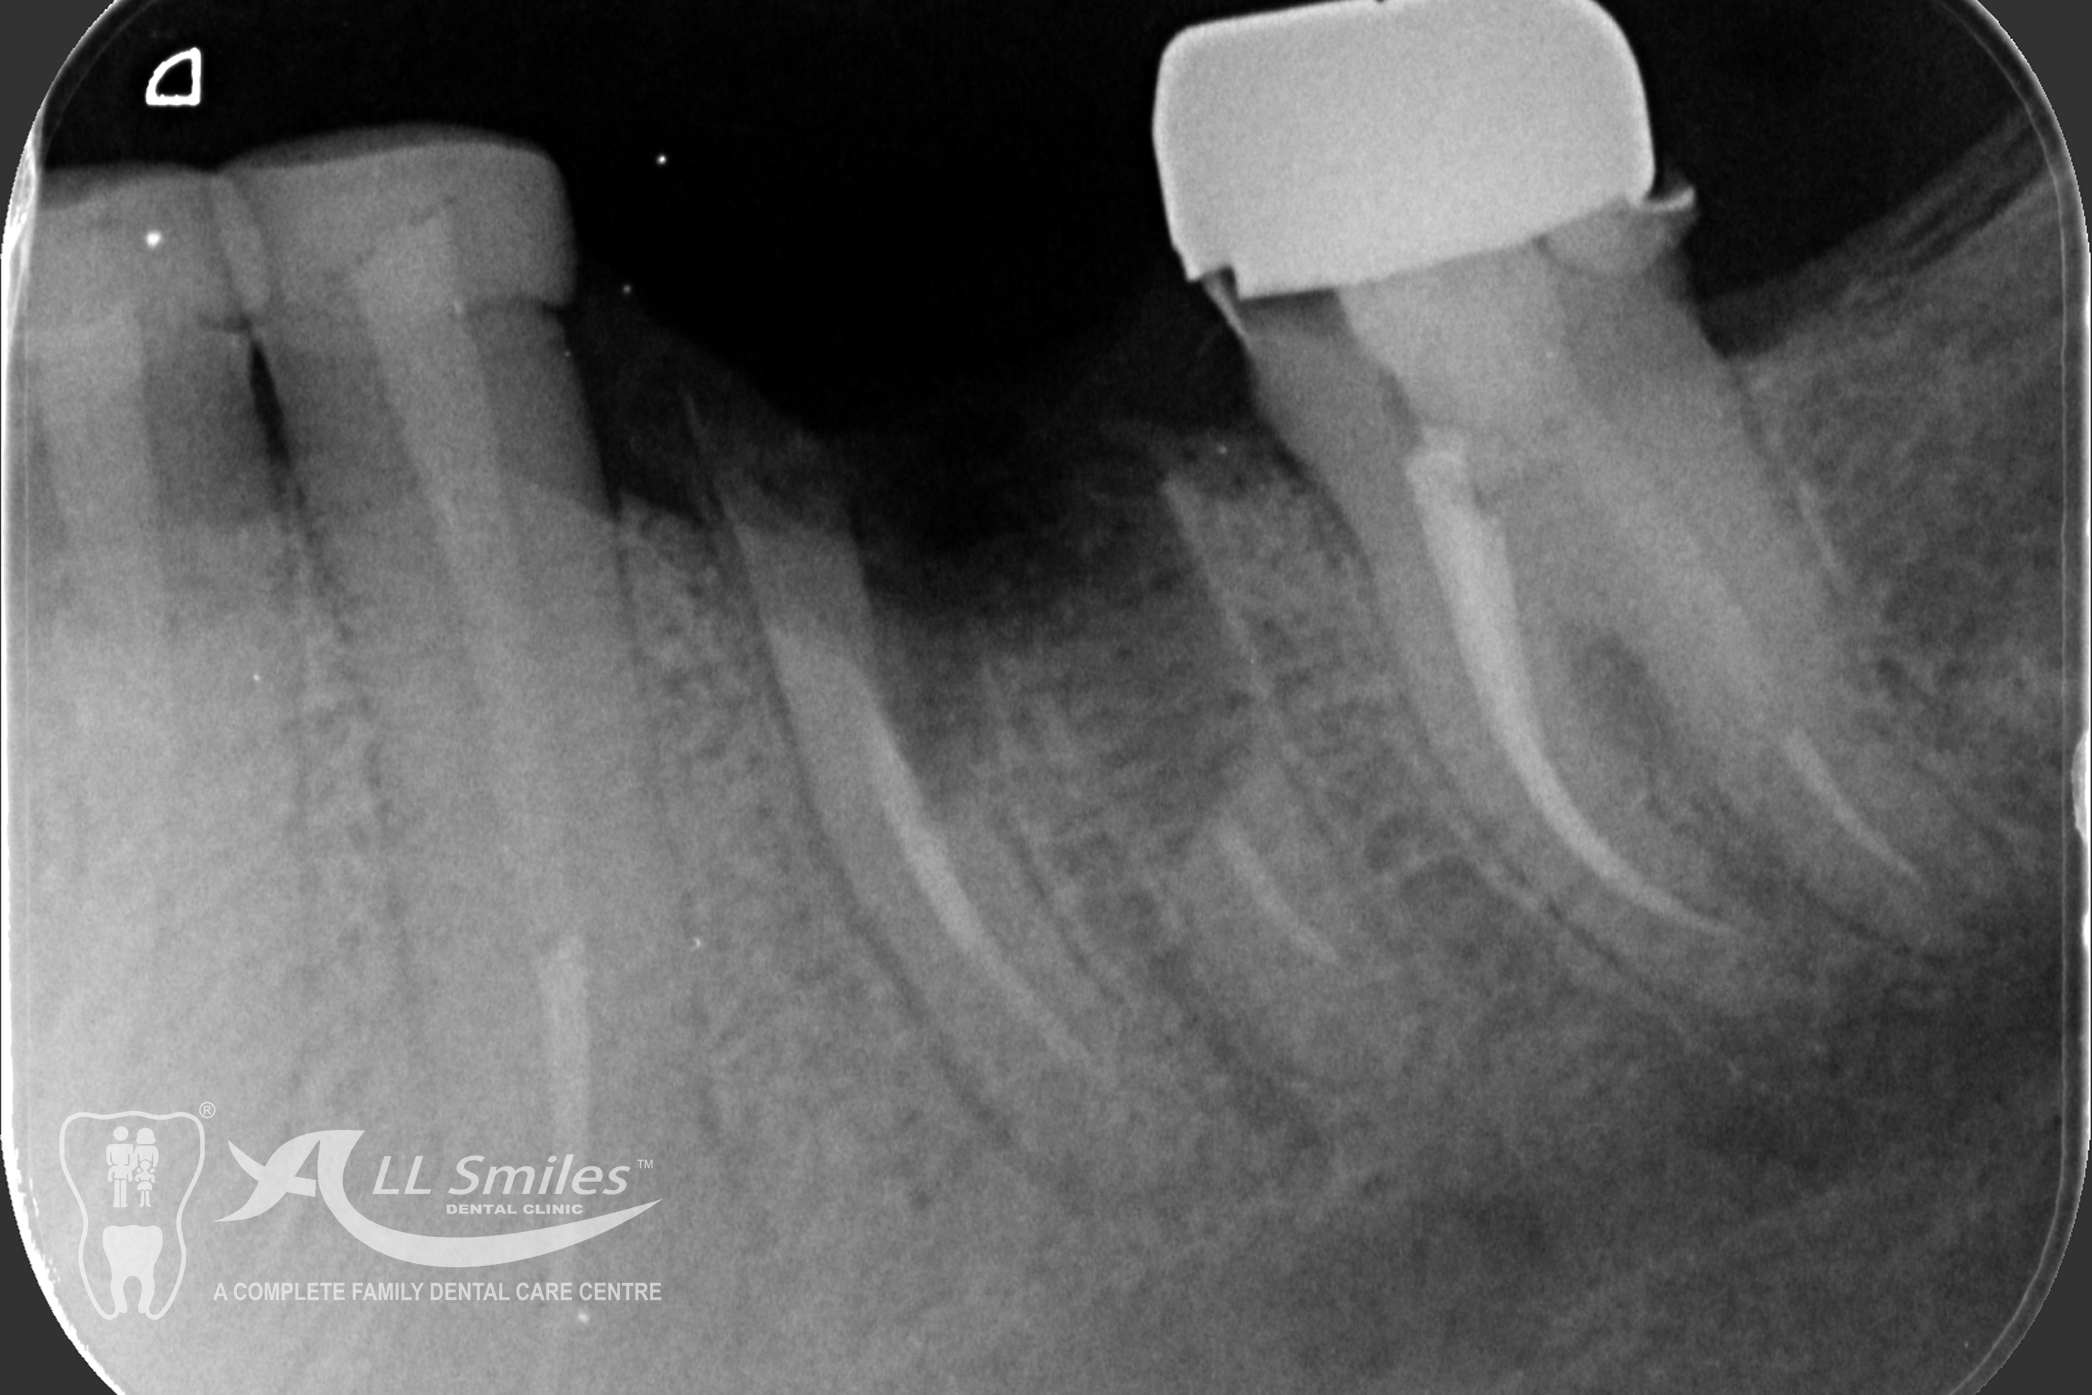

Successful tooth implant procedures require a foundation of healthy bone and gums. Before starting an implant procedure, we’ll assess your health and work with you to create a plan to resolve gum disease or other issues. Expect your first visit to take about 90 minutes and include an exam, x-rays, thorough cleaning, and plenty of time to speak with your dentist.

The dental implant procedure is divided into stages. The first stage involves the placement of the implant into the jawbone, which usually takes 1-2 hours. After this, there is a healing period of 6-8 weeks during which the implant fuses with the surrounding bone tissue. Once the implant has healed, a small connector called an abutment is attached to the implant, followed by the attachment of a dental crown, bridge, or denture.